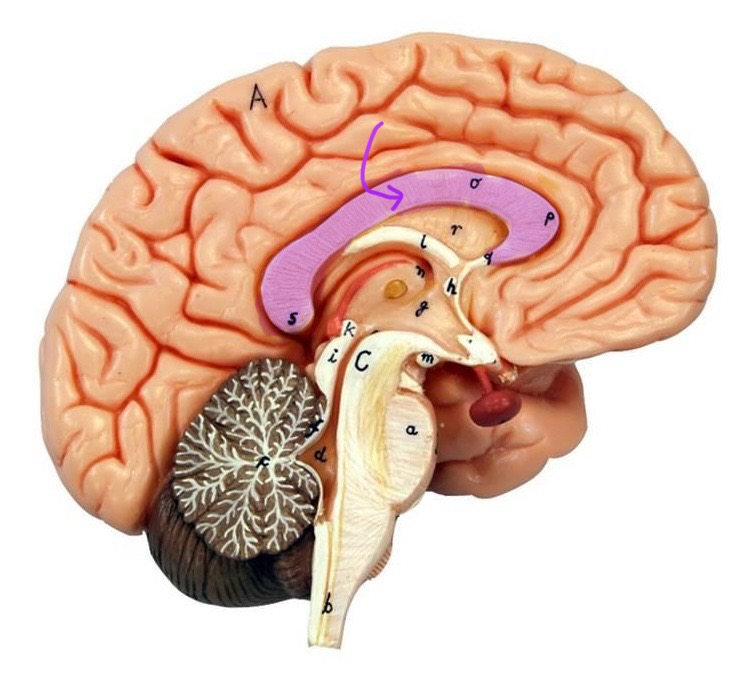

What is D?

lateral ventricle

Imagine thin membrane separating the 2 lateral ventricles

septum pellucidum

What is C?

3rd ventricle

What is B?

cerebral aqueduct

What is A?

4th ventricle

What is below A at the very end?

central canal (spinal cord)

What is C?

midbrain

tectum (corpora quadrigemina): superior colliculus

tectum (corpora quadrigemina): inferior colliculus

What is a?

pons

medulla oblongata

intermediate mass of thalamus

hypothalamus

What is the pink bulb?

pineal gland

corpus callosum

fornix

What is A?

cerebral cortex

cerebral tracts

cerebral hemispheres

longitudinal fissure

What are these ridges?

gyri

What are these shallow grooves?

sulci

Divides parietal from frontal lobe

central sulcus

precentral gyrus

postcentral gyrus